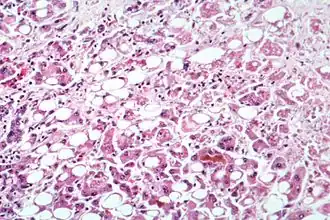

Microscopie

Une hépatite chronique est une pathologie nécrotico-inflammatoire du foie, de sévérité variée, excluant les maladies biliaires (cholangiopathies), la maladie alcoolique (hépatopathie alcoolique) et les stéatohépatites.